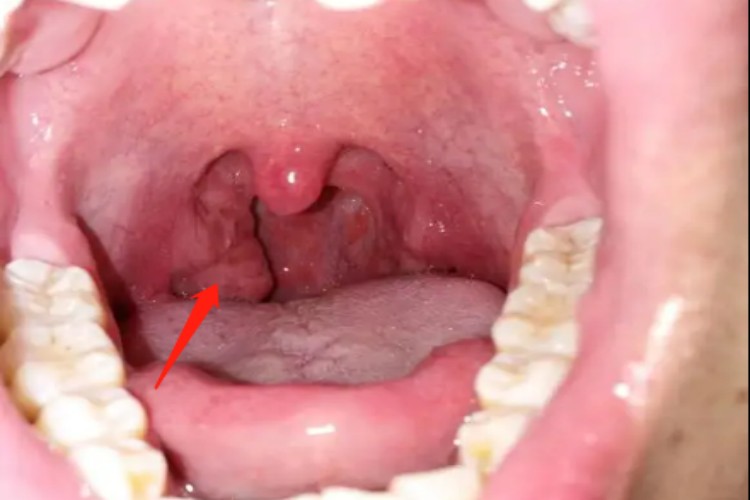

淋菌性咽炎属于无并发症淋病,约80%的患者没有症状,即使有症状也非常轻,主要表现为急性咽炎或急性扁桃体炎,有咽干、咽部不适、咽痛以及吞咽痛等,偶伴发热和颈淋巴结增大。

淋菌性咽炎的治疗,可遵医嘱肌内注射头孢曲松钠、头孢噻肟钠、大观霉素等。口腔局部可选用消炎防腐含漱剂,如复方氯己定含漱液等。